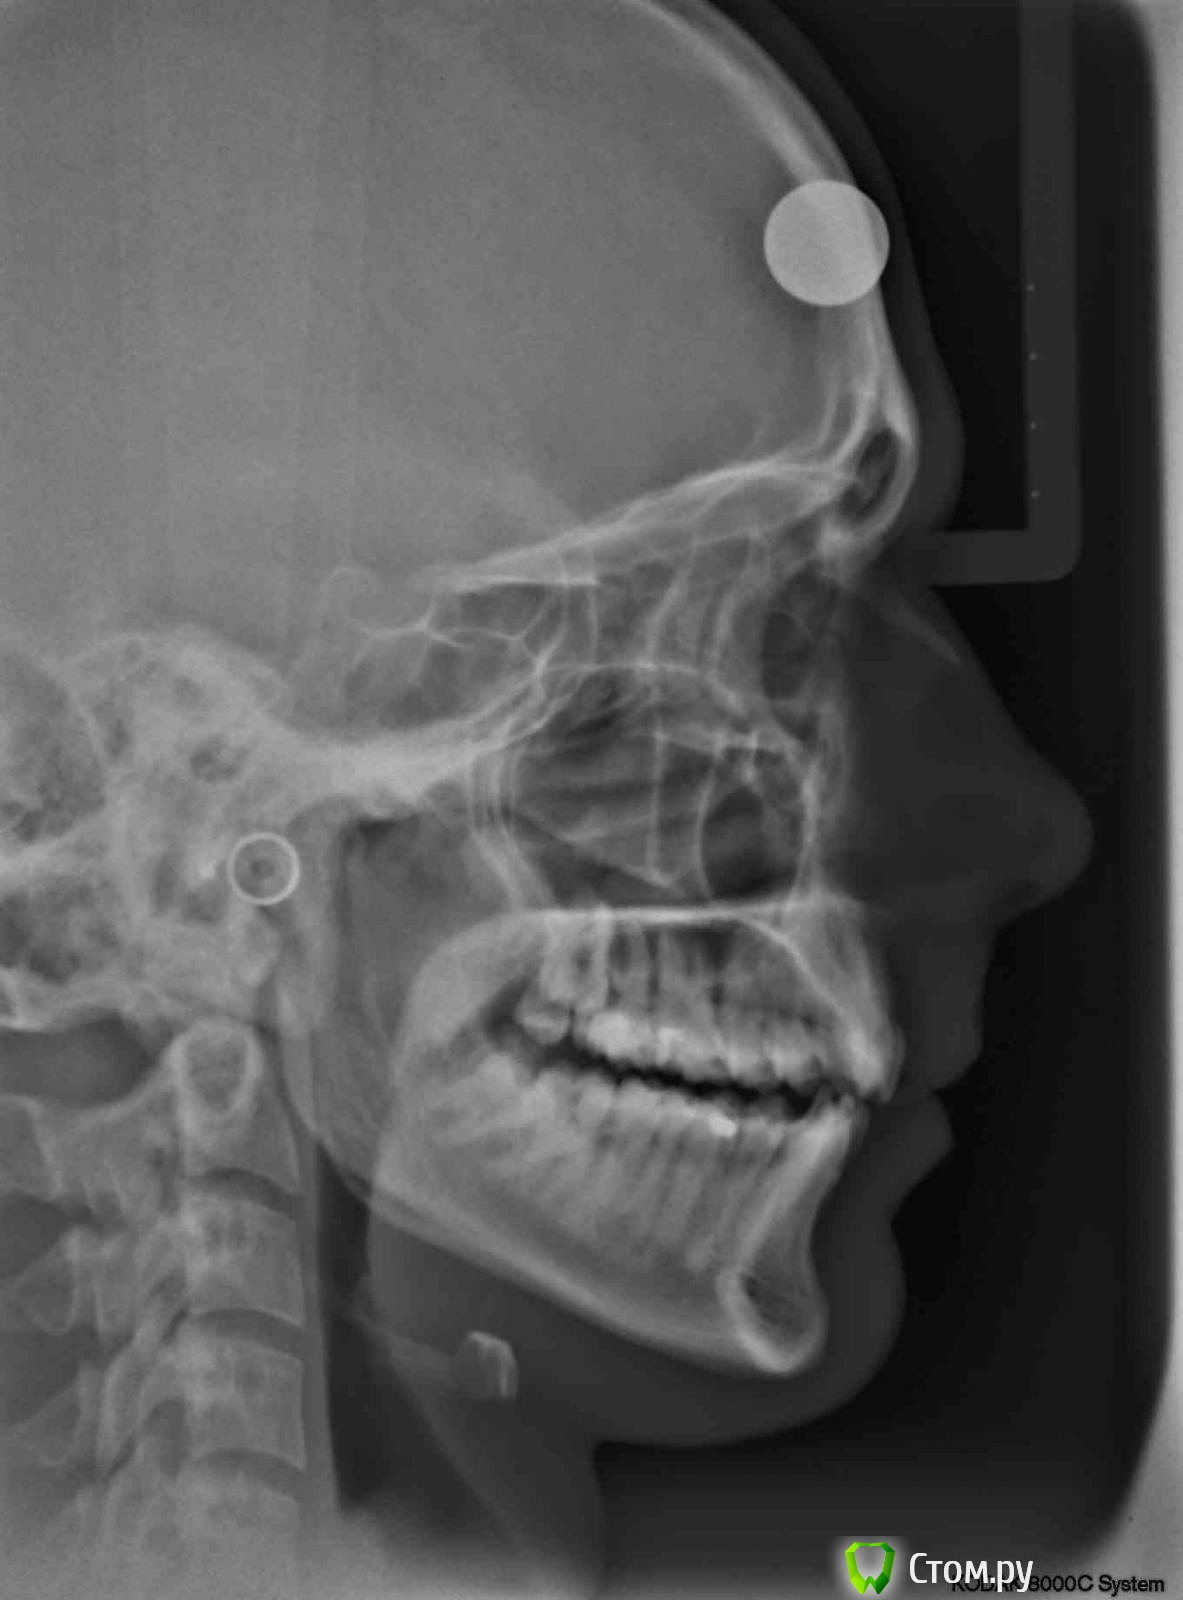

Татьяна_200 Опубликовано 20 августа, 2014 Поделиться Опубликовано 20 августа, 2014 Подскажите пожалуйста, есть ли необходимость удалять верхние восьмерки? Вроде скученности вверху особой нет. Удаление восьмерок непростое всегда, рядом пазухи , стоит ли ? Ссылка на комментарий

Korel Опубликовано 25 августа, 2014 Поделиться Опубликовано 25 августа, 2014 Вам надо убирать ВСЕ 4 восьмёрки. Начните с нижних. Ссылка на комментарий